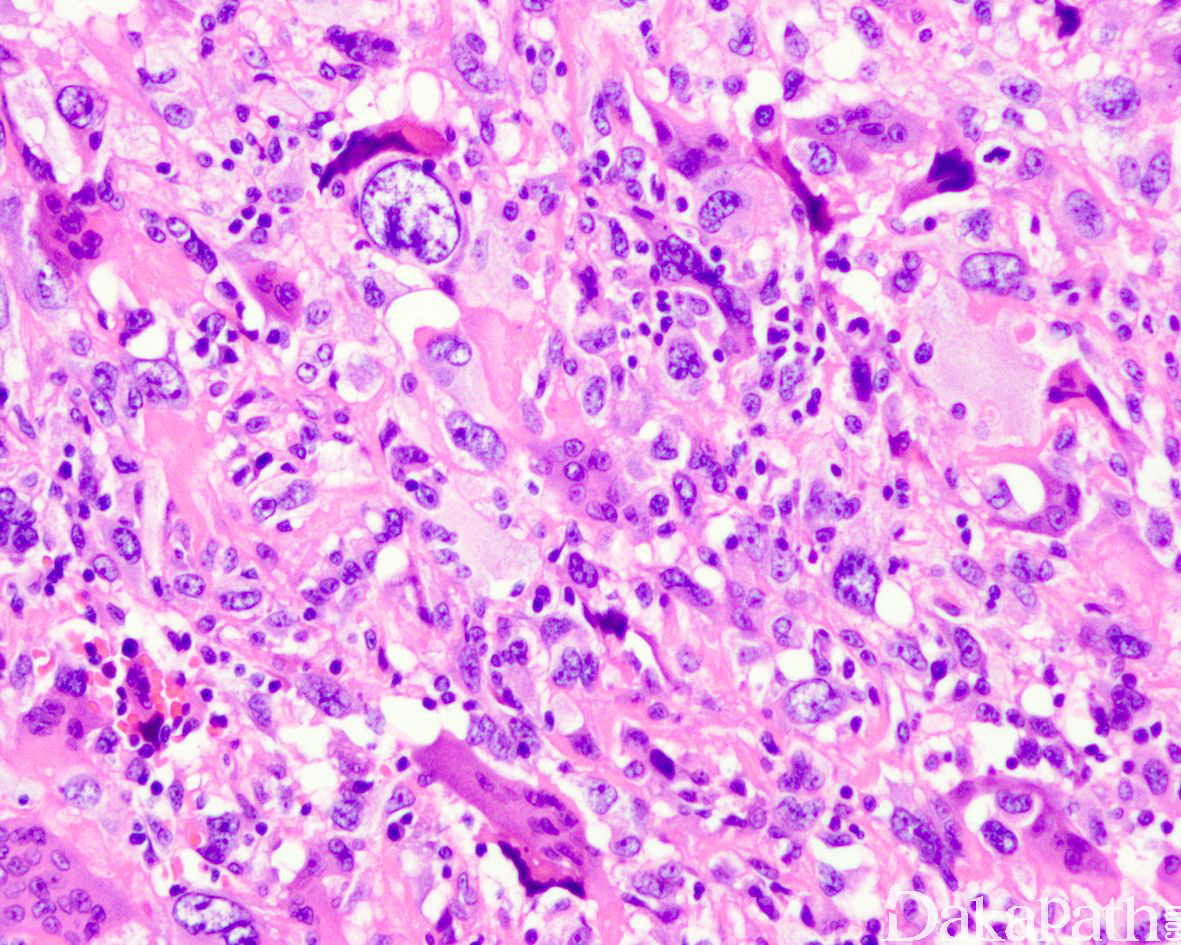

特点为大的多形性细胞,伴有大而深染的细胞核和明显的核仁;

大量核分裂象,常见非典型性核分裂象;

(1)显现奇异的肿瘤巨细胞;

(2)大量核分裂象,包括非典型核分裂象;